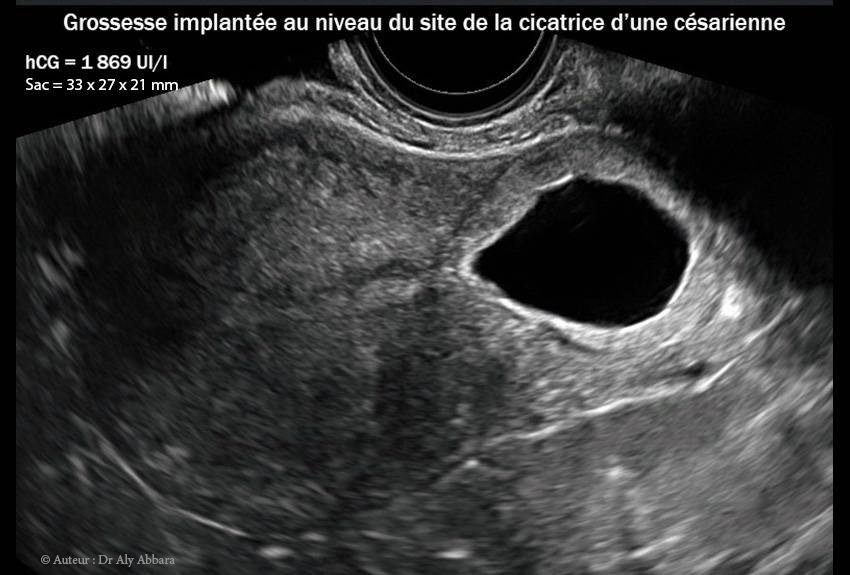

Grossesse ectopique intra-murale sur utérus cicatriciel

• Images échographiques par voie endovaginale montrant un sac gestationnel d'une grossesse débutante et partiellement intramurale, implantée dans le site de la cicatrice de l'hystérotomie segmentaire transversale d'une ancienne césarienne.

• L'aspect du sac gestationnel au 6e semaine post traitement médical par méthotrexate : il mesure 35 x 30 x 25 mm de diamètres (= 13,7 cm3) ; le dosage de β-hCG plasmatique était égal à 1869 UI/l.

Le 04.10.2012 (5+2 SA) -J0- : la patiente consulte aux urgences pour légère douleur pelvienne sans métrorragie ; l'examen clinico-échographique permet de mettre en évidence le diagnostic d'une grossesse débutante implantée dans le site de l’ancienne cicatrice de l’hystérotomie segmentaire transversale de l'ancienne césarienne ; il s'agissait d'un sac gestationnel de (20 x 12 8,5 mm) de diamètre, contenant une vésicule vitelline sans image embryonnaire.

Dosage de BHCG à 13 583 UI/l.

15.11.2012 = (J42) = 6 S 1 869 UI/l 35 x 30 x 25 mm = 13,7 cm3 J0